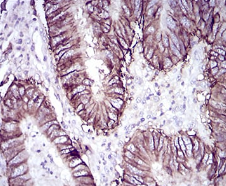

CDH17单克隆抗体[7D10E]

CDH17 Mouse Monoclonal antibody[7D10E]

Immunogen :   Purified recombinant fragment of human CDH17 (AA: extra(600-707)) expressed in E. Coli.

IHC    1/200 - 1/1000